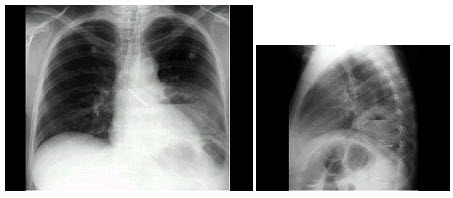

57、单项选择题

女,36岁,发热,胸痛咳脓痰10余天,胸片如图,最可能的诊断为()